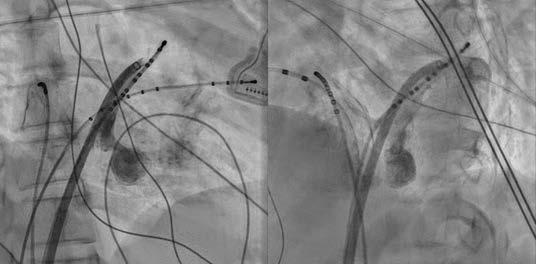

AVRT with concealed left posterior septal AP,於是在RV pacing時,我們先從RPS region開始mapping沒有發現有 VA fusion site,然後我們就到retrograde transaortic到LPS region mapping也沒有找到VA fusion的位置,接著我們 的電燒導管在 CS 裡 mapping 時突然掉進 MCV ,這裡發

現有VA fusion (圖八),由於可能很靠近coronary artery

擔心用 RF ablation 會造成 coronary artery stenosis or occlusion(2) ,我們在 ablation 前有先做 coronary angiogram (圖九),coronary artery離VA fusion site都有超 過5 mm,所以我們就使用7F non-irrigated RF catheter在 MCV VA fusion site進行ablation,但是沒有效果,接著 我們做了 CS venogram 發現有一個 CS diverticulum 在 MCV (圖十)(3),我們就把電燒導管移到diverticulum的 neck ( 圖十一 ) ,可以看到 VA fusion ,在 RV pacing 下 50W/50oC 電燒一開始 0.7 秒就 VA block ( 圖十二 ) ,接著 RF booster 120 seconds,post-ablation EP study只有看到 在 V pacing 時有 one fast-slow echo beat , antegrade conduction 有 dual AVNs ,但無法誘發任何 AVNRT or AVRT。病患接受完電燒後,沒有再有心悸的症狀。 (圖一)、發作時12 lead ECG (圖二)、12 lead ECG after adenosine use

)、冠狀竇攝影發現

)、VA block within 1 second during RF ablation when RV pacing

(圖九 (圖十一)、X光透視成功電燒的位置在diverticulum neck及3D圖上的成功位置 (圖十二 (圖十 CS diverticulum